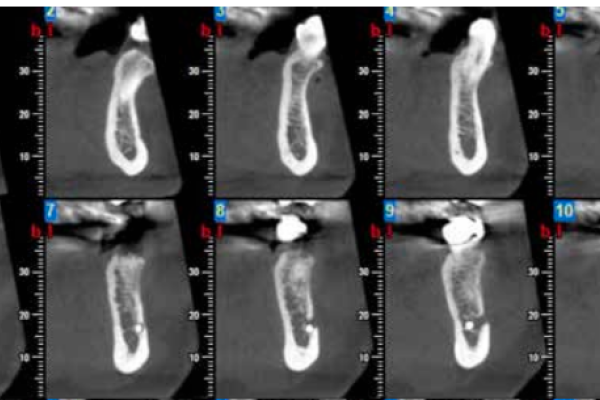

Comparative densitometric analysis between a new bone graft material composed of calcium phosphate vs. bovine hydroxyapatite in alveolar ridge preservation. A pilot study

Evaluación de la cantidad de hueso neoformado al emplear materiales de relleno en elevación de seno maxilar con abordaje lateral